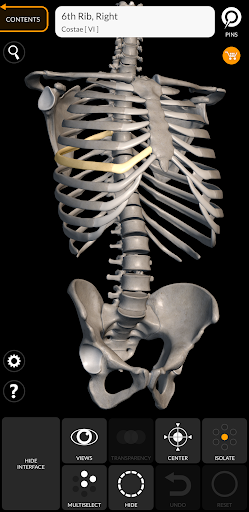

"Skeleton | 3D Atlas of Anatomy" is a next generation anatomy atlas in 3D which gives you availability of interactive highly detailed anatomical models!

Each bone of the human skeleton has been reconstructed in 3D, you can rotate and zoom in on each model and observe it in detail from any angle.

HIGHLY DETAILED ANATOMICAL 3D MODELS

• Skeletal System

• Accurate 3D modeling

• Surfaces of the skeleton with high resolution textures up to 4K

• Rotate and Zoom every model in the 3D space

• Division by regions for a clear and immediate visual of each structure

• Possibility to hide every single bone

• Interactive Pin allow visualization of the term relative to every anatomical detail